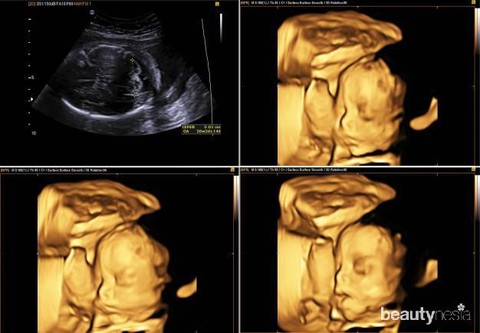

Tak hanya berdampak pada tubuh, stres selama kehamilan juga dapat memiliki dampak buruk pada janin. Oleh karena itu, sangat disarankan bagi bumil untuk mengelola stres yang sedang dialami. Untuk itu bumil perlu mencari tahu penyebab stres terlebih dahulu, agar dapat diatasi dengan baik. Karena jika stres dibiarkan berlarut dikhawatirkan dapat menjadi parah dan berdampak buruk pada janin. Diantaranya sebagai berikut ini.